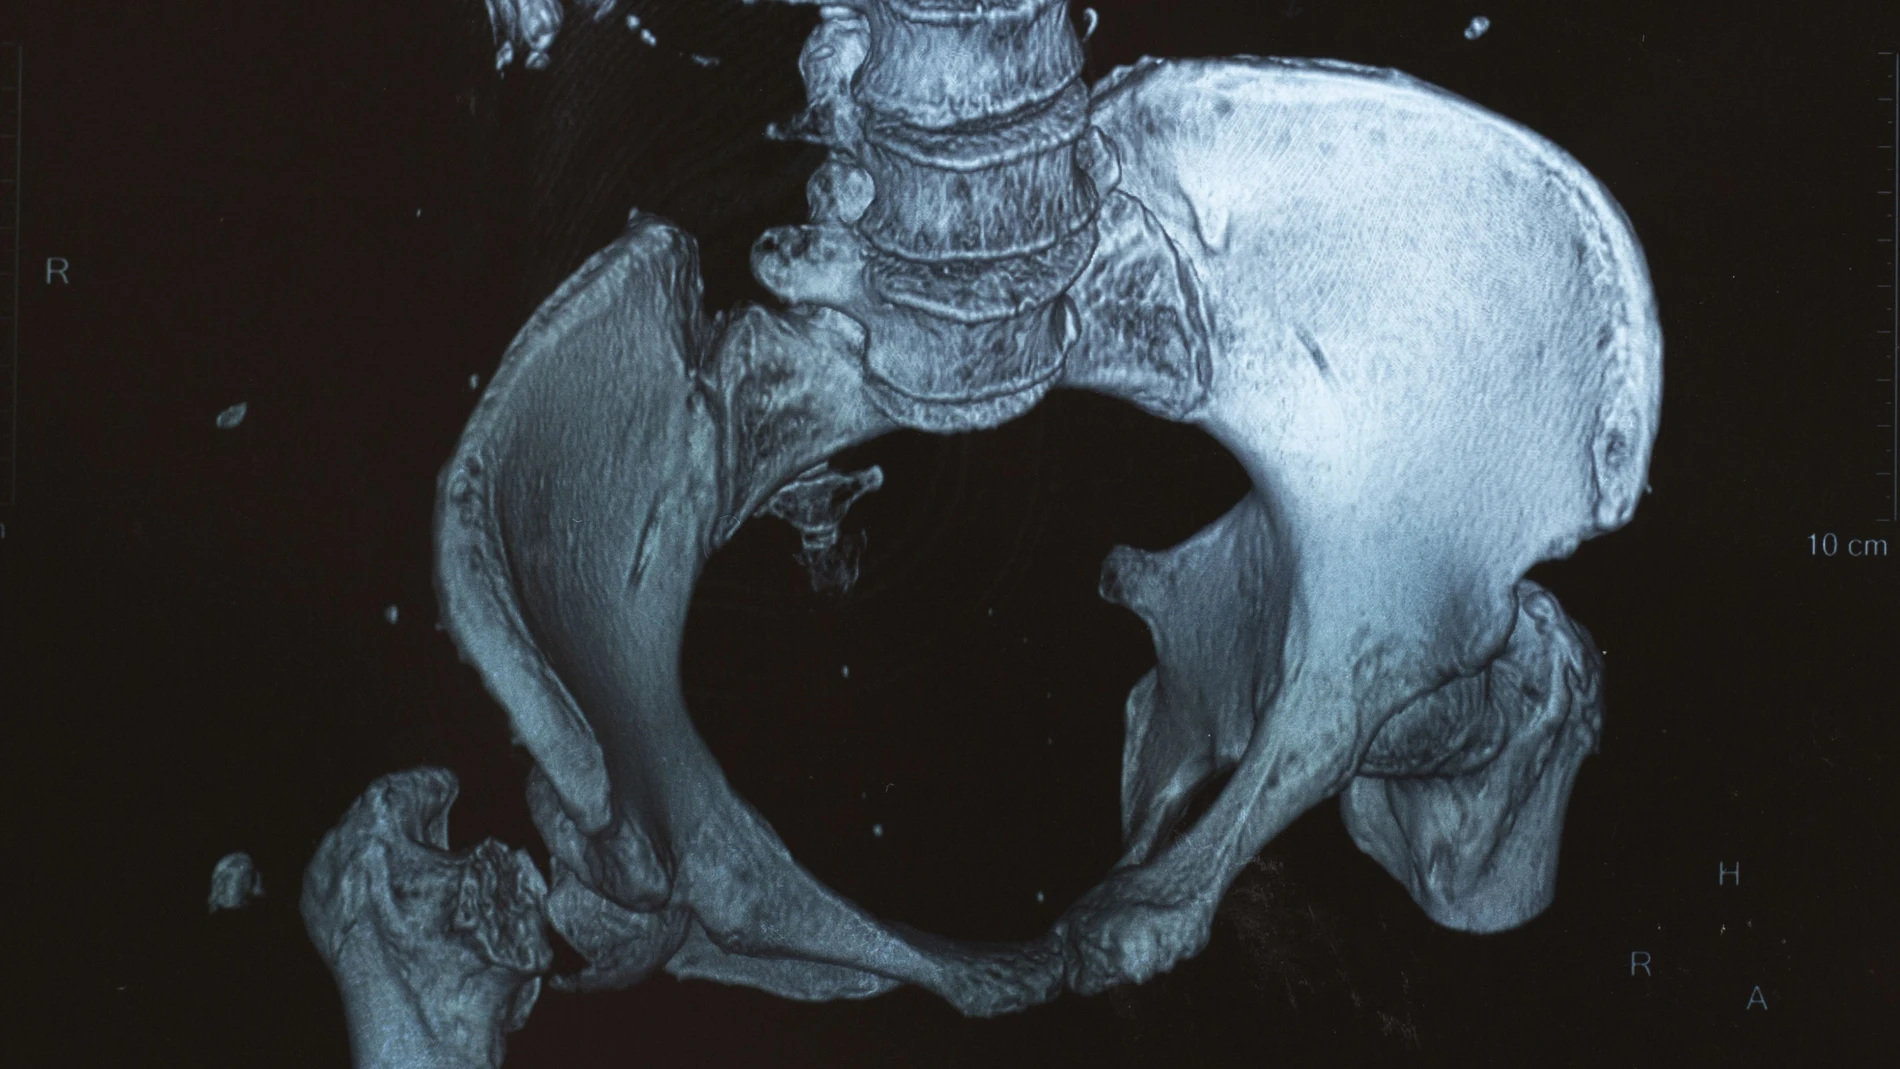

Explicar qué es el mieloma y como vivimos los pacientes no es tarea fácil. Es un cáncer de las células plasmáticas, las defensas de nuestro cuerpo, que viven en la médula ósea (el tuétano de los huesos) y que comienzan a proliferar de forma desmesurada no dejando que cumplan su función frente a las infecciones, provocando también anemia y daño renal además de daño óseo porque es un cáncer que “se come los huesos”, es una de sus características principales. El cuerpo de un paciente con mieloma múltiple se llena de lesiones líticas, pequeños agujeritos en los huesos que pueden llegar a convertirse en verdaderos agujeros que nos va dejando sin partes de nuestro cuerpo, perdemos la función de reparación y regeneración propia de los huesos.